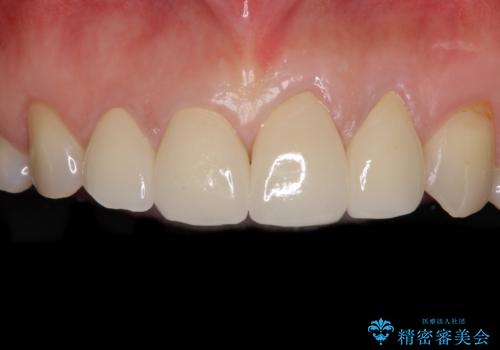

ブリッジの支台歯は2本とも神経を取り除いている歯であるため、咬合力の強い方ですと、支台歯も歯根破折をするリスクがあります。

今回はそれほど咬合力が強いとは思われなかったため、ブリッジによる補綴治療を行いましたが、念のため、就寝時にはナイトガードとしてマウスピースを装着するようお願いしました。